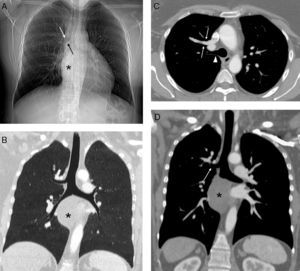

A) Radiografía de tórax en la que se observa una masa mediastínica (asterisco) que oblitera la línea pleuro-ácigos-esofágica y un posible bronquio traqueal (flechas). B) Reconstrucción coronal minIP (proyección de mínima intensidad) que confirma la existencia del bronquio traqueal. Nótese la masa mediastínica (asterisco). C) Imagen axial de TC de tórax con contraste intravenoso en la que se visualiza un drenaje anómalo de la vena pulmonar del lóbulo superior derecho en la vena cava superior (flechas) y el bronquio traqueal (cabeza de flecha). D) Imagen coronal oblicua de TC de tórax con contraste intravenoso en la que se aprecia el bronquio traqueal (flecha) y la masa mediastínica (asterisco).

Presentamos el caso clínico de una mujer de 45 años diagnosticada de NF1, no fumadora, que presentaba una disfagia secundaria a un tumor mediastínico posterior que comprimía el esófago torácico, compatible radiológicamente (mediante resonancia magnética) con un tumor neurogénico dependiente del nervio vago derecho. En la exploración física únicamente destacaban manchas «café con leche» en la superficie cutánea y varias cicatrices en la espalda y pared abdominal en relación con resecciones previas de neurofibromas en dichas localizaciones. Dada la sintomatología de disfagia progresiva se decidió intervenir quirúrgicamente a la paciente del tumor mediastínico posterior. En la radiografía de tórax preoperatoria (fig. 1A) se observó un posible bronquio traqueal (BT), por lo que se decidió completar dichos estudios con una tomografía computarizada (TC) de tórax, confirmándose la existencia del BT y su asociación inesperada con un drenaje venoso pulmonar anómalo parcial (DVPAP). El DVPAP consistía en un drenaje de la vena del lóbulo superior derecho en la vena cava superior (fig. 1B-D).